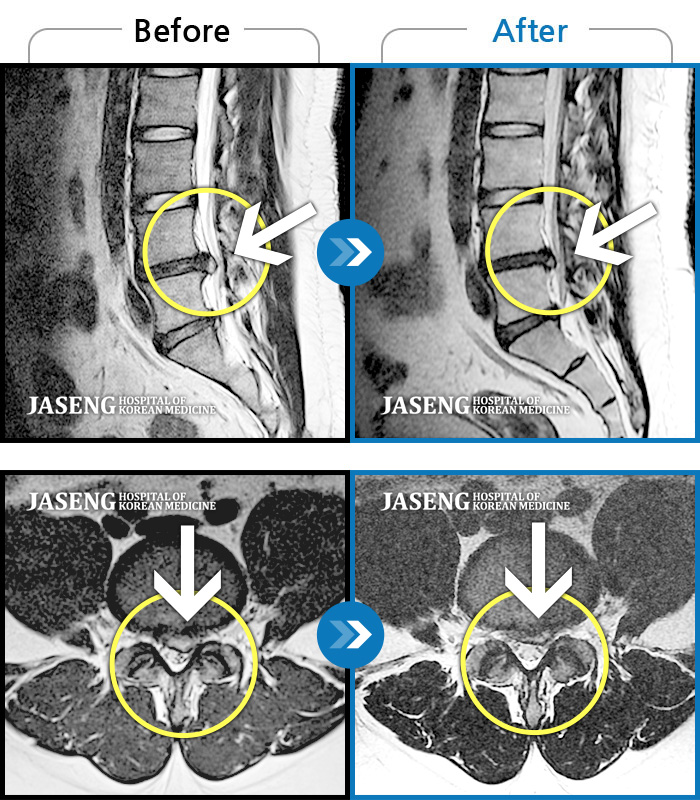

25년 1월 허리통증이 시작되고 잠을 잘수도없고 걸을 수 없을만큼의 상태가 되었을때 다시 김태용 원장님께 진료를 받고 예전 허리수술의(4번5번)(3번4번)디스크탈출증 재발과 협착증의 진단을 받고 지금까지 기나긴 여정의 입원 치료를 하며 곧 퇴원을 앞두고 있습니다.

눈내릴때 입원하여 꽃피는 춘삼월에 퇴원을 하게 된거죠~ 입원기간이 길어지며 주변의 간섭도 늘어갔고 저 또한 힘들어 포기하고 싶을때도 있었지만 원장님의 따듯한 말과 매일 같이 세심하게 환자의 상태를 파악하고 숙련되고 정확한 침치료와 약처방으로 지금은 일상생활에도 무리가 없을정도로 많이 호전 되었습니다.